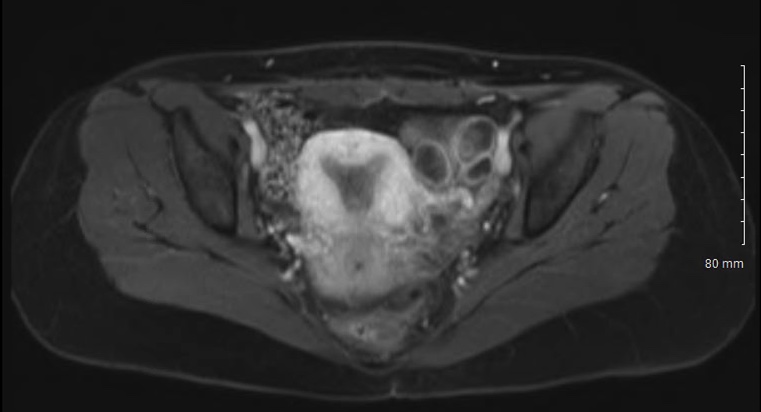

Fig. 2.Abdominal MRI performed one week after oocyte retrieval, demonstrating disappearance of the fluid.

Fertility preservation in patients suffering from borderline ovarian tumors have been described in the literature [5, 7, 16]. Gonadotropin stimulation of ovarian tumor cells could in theory cause tumor cell growth and metastasis to occur. However, up until this point no proof of such has been noted. This was assumed to be due to the short duration of gonadotropin stimulation. However, this is the first time in the medical literature that a supra-facial large fluid collection occurred during ovarian stimulation of an ovarian tumor patient, with the absence of ascites or ovarian hyperstimulation syndrome. The subject had only 4 follicles stimulated, relatively low serum estradiol levels and no ascites was present. It is also extremely unlikely that ovarian hyperstimulation syndrome was present on the day of oocyte retrieval because it usually occurring several days latter. Interestingly, the fluid collection was self-limited and disappeared post ovarian stimulation. Regrettably, this occurred prior to obtaining a cytological specimen of this fluid for assessment. Our hypothesis is that during the emergency operation for the cyst rupture, before the stimulation cycle started, low malignant potential ovarian cells spread via the laparoscopy port to the subcutaneous space, although of such we cannot be certain.

As for the fluid collection being induced by ovarian stimulation, several unique issues occurred. First of all, the fluid collection reabsorbed on its own and did not re-occur with the subsequent stimulation cycles. We suspect this reflects the propensity for low malignant potential tumors not to metastasize in an invasive fashion. Although, these tumors seed cells to the peritoneal cavity, these cells have a life cycle and undergo spontaneous apoptosis. We hypothesize this likely occurred to the cells causing the fluid collection in the subcutaneous space, however, no cytology specimen was obtained since the fluid reabsorbed prior to this being done. Whether ovarian stimulation increases invasive metastasis of low malignant potential ovarian tumors is unknown. There is a paucity of evidence regarding controlled ovarian hyperstimulation in patients with borderline ovarian tumor. This tumor has both receptors for estrogen as well as progesterone, and there may be detrimental effects of controlled ovarian hyperstimulation on borderline ovarian tumor growth [4]. It is possible that hormone production seen with ovarian stimulation may induce an apoptosis of these borderline ovarian tumor cells [4] or that they would have undergone apoptosis anyways, since this may be the nature of such a tumor. In future cases, use of an aromatase inhibitor may prevent growth of the tumor cells by decreasing endogenous estrogen levels and should have been considered in this case. Aromatase inhibition was not initiated with the stimulation protocol due to the propensity of low malignant potential tumor cells to not metastasize.

The exact cause of the subcutaneous fluid accumulation cannot be known with certainty because it reabsorbed itself prior to a cytological specimen being collected. However, the accumulation of subcutaneous fluid in a women undergoing ovarian stimulation is unique in the literature.